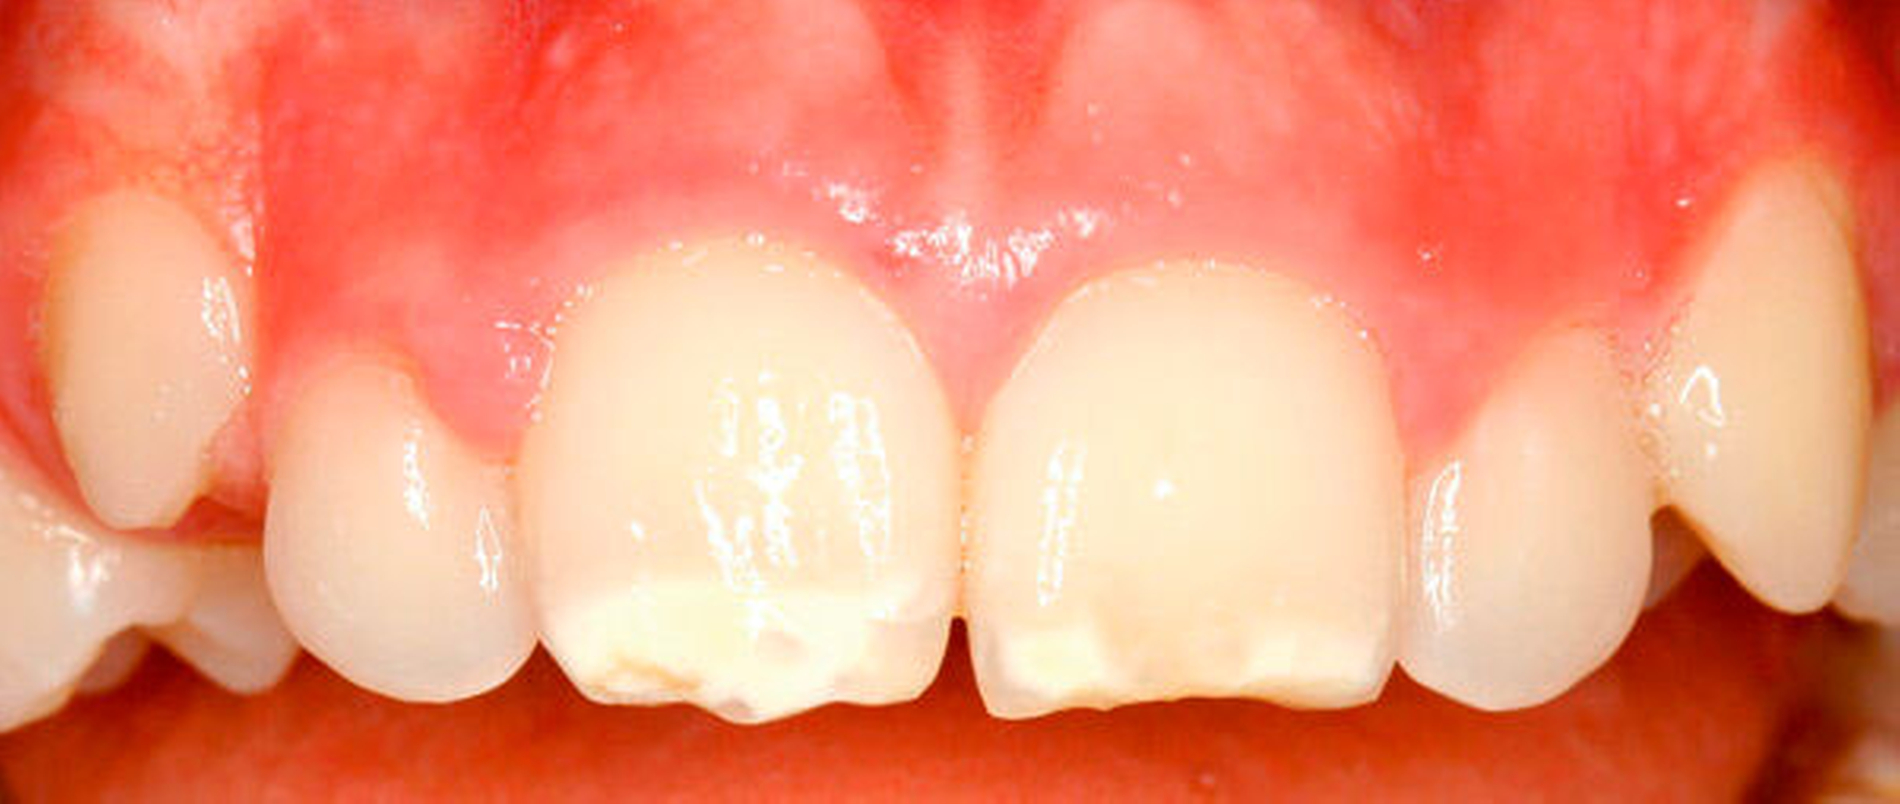

Die MIH ist als Erkrankung der ersten Molaren und der Schneidezähne definiert, wobei mindestens ein erster Molar betroffen sein muss, die Einbeziehung von Schneidezähnen hingegen optional ist [1]. Die entwicklungsbedingten Zahnhartsubstanzdefekte gehen auf Störungen während der Zahnentwicklung zurück, verbunden mit einer ungenügenden Rückresorption von Wasser und Proteinen während früher Phasen der Schmelzbildung. Es resultiert ein mindermineralisierter Schmelz, der zu einer unzureichenden mechanischen Belastbarkeit des Schmelzes bis hin zu Schmelzabsprengungen führen kann. Die MIH imponiert daher oft als Hypoplasie, ist aber eine Hypomineralisation (Tabelle 1). Da die MIH epidemiologisch gut an kariesfreien Zähnen erkennbar ist, wenn noch keine Restaurationen vorliegen, wurde dieses Krankheitsbild in der DMS V exklusiv bei den 12-jährigen Kindern erhoben.

Ganz überwiegend (81,0 Prozent) lag bei den Probanden mit einer MIH, gemessen an den ersten Molaren und Schneidezähnen, ein geringer Ausprägungsgrad vor, gefolgt von umschriebenen Schmelzeinbrüchen (9,8 Prozent) und atypischen Restaurationen (7,4 Prozent). Großflächige Schmelzeinbrüche und Extraktionen aufgrund von MIH wurden nur in seltenen Fällen beobachtet (Tabelle 2).